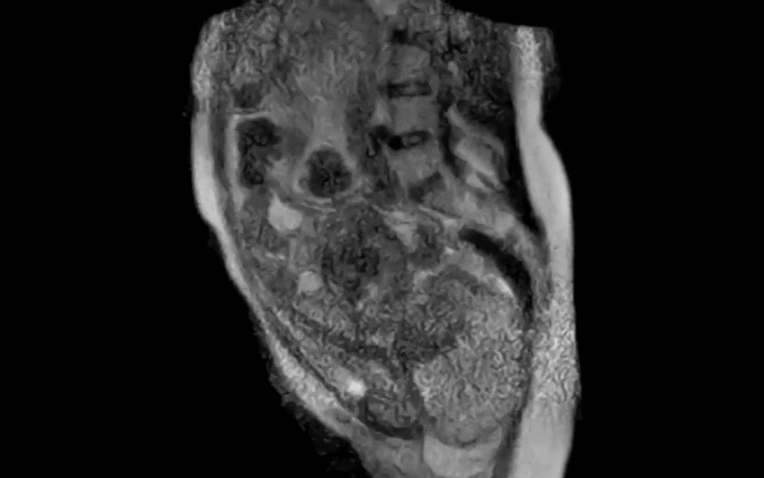

Quay lại với ca sinh nở, các nhà khoa học tại Bệnh viện Đại học Charité, Berlin, Đức đã ghi lại 45 phút cuối của quá trình chuyển dạ , sau đó rút gọn thành một đoạn video dài 25 giây. Hình ảnh cho thấy rõ vị trí thai nhi, sự di chuyển của em bé qua ống sinh và sự thay đổi của các cơ quan trong cơ thể người mẹ khi rặn sinh.